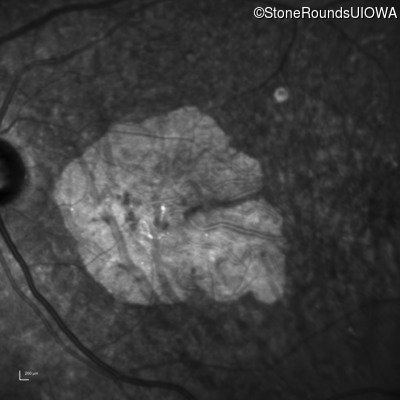

Infrared Fundus Photograph - Left - 20/160 sc

Exemplar